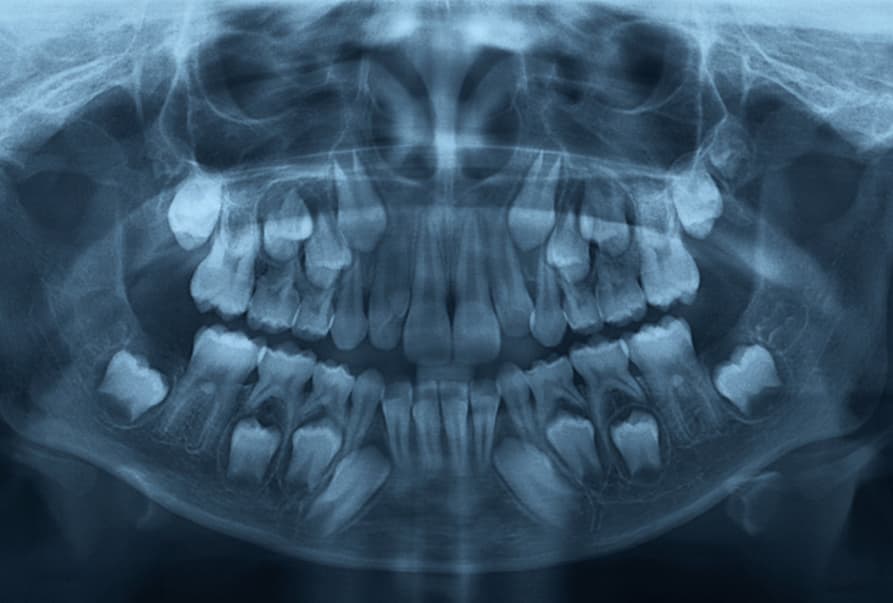

تشخیص دندانهای اضافی در گذشته فقط با تکیه بر رادیوگرافیهای پانورامیک (OPG) یا پریاپیکال دوبعدی انجام میشد که محدودیتهای بسیاری داشتند. در این تصاویر، دندانها روی هم همپوشانی داشتند و تشخیص اینکه دندان اضافه در سمت زبانی (پالاتال) دندان اصلی قرار دارد یا در سمت لبی (باگال)، بسیار دشوار بود. بااینحال در سال ۲۰۲۵، استاندارد طلایی تشخیص، استفاده از فناوری “اسکن CBCT” یا توموگرافی کامپیوتری با پرتو مخروطی است.

فناوری سهبعدی CBCT به جراح اجازه میدهد موقعیت دقیق دندان اضافه را نسبت به ریشههای دندانهای دائمی، اعصاب و سینوسها با دقت میلیمتری مشاهده کند. این تفاوت مانند تماشای سایه یک جسم روی دیوار در مقایسه با در دست گرفتن و چرخاندن همان جسم است. در روش دوبعدی، جراح ممکن است مجبور شود برای یافتن دندان اضافه، استخوان زیادی را بردارد، ولی با نقشه راه دقیقی که CBCT ارائه میدهد، دسترسی مستقیم، کمتهاجمی و ایمن امکانپذیر میشود که ریسک آسیب به ریشههای حساس دندانهای مجاور را به صفر نزدیک میکند.